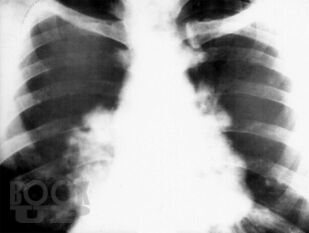

В монографии на современном научном уровне изложены вопросы истории изучения саркоидоза, представлены вопросы его этиологии, патогенеза, а также эпидемиологические, морфологические, клинические и функциональные аспекты его проявления. Авторами разработаны и внедрены в практику простые, повсеместно доступные, высокоинформативные и интегральные новые диагностические критерии оценки состояния гомеостаза у больных саркоидозом на основе оценки состояния и динамики гематологических показателей. Корректировка показателей гомеостаза (типов адаптационных реакций организма, типов реактивности организма, лейкоцито-лимфоцитарного индекса, показателей энтропии и избыточности форменных элементов белой крови и показателей белковых фракций крови) позволила внедрить в практическую работу математические модели и графики факторных пространств для проведения персонифицированного назначения активаторов защитных систем организма, контроля активационной патогенетической терапии и повысить эффективность лечения саркоидоза.